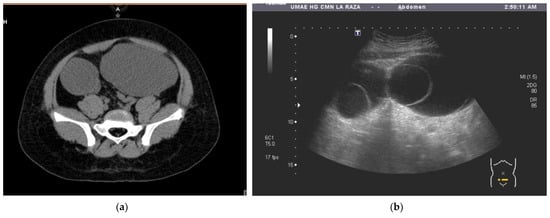

The patient was referred to our hospital, where a second ultrasound found anechoic abdominal lesions with round, dense material inside. A subsequent CT showed two pelvic lesions of 20 HU, one of 174 cc (right ovary) and the other of 333 cc (left ovary). The left one had a round interior image of 250 HU inside. The radiological diagnosis was adnexal vs. mesenteric cystic tumors (Figure 1a,b). Blood tumor markers were negative (Table 1).

Figure 1. (a) Tomography image of the two pelvic tumors, A: Anterior; (b) ultrasound image of a pelvic tumor, T: Transductor.